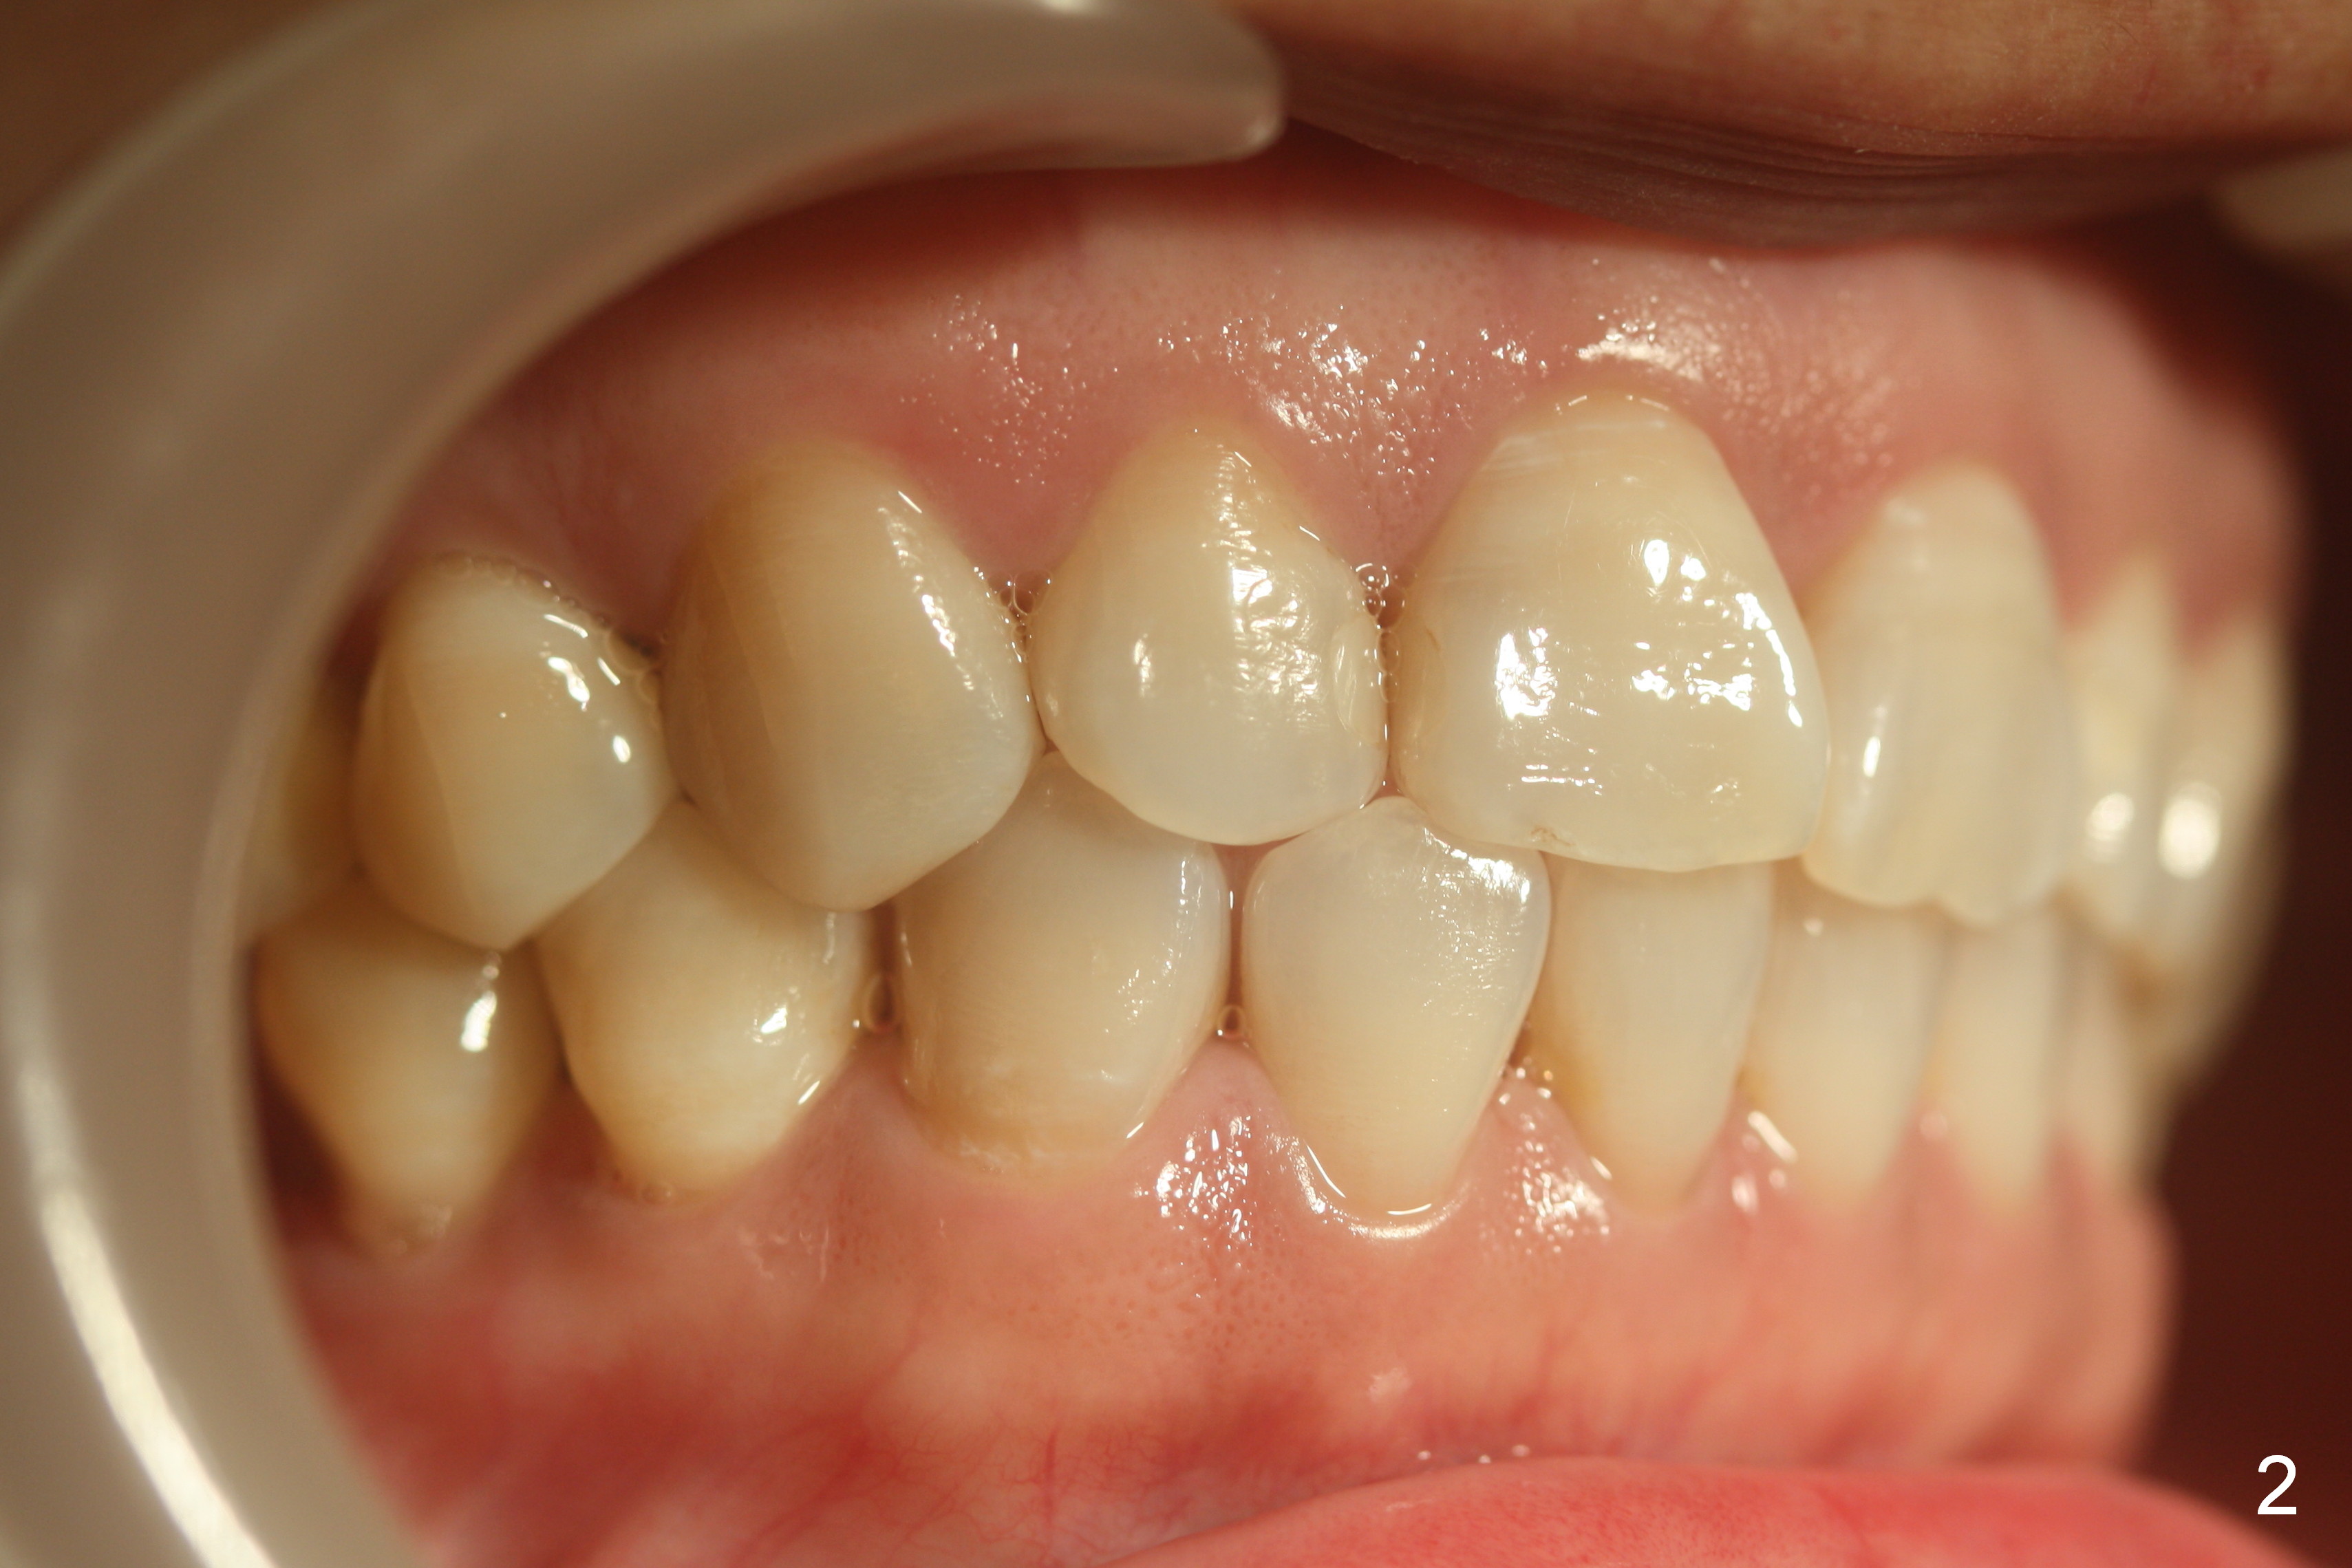

Four weeks of using open coil spring between #29 and 31, these teeth seem to have rotated (Fig.8,9 curved arrows). After placing a longer spring and the same arch wire, power chains are installed to close the anterior diastema (Fig.10 ^). The patient notes the divergence between #20 and 21 (Fig.11). To correct the latter, either place #20 bracket more distal (Fig.11 *) or place power chains between these teeth only. To facilitate #31 distalization (Fig.13), place lingual buttons (Fig.12 red) in the mesial surface of #31 and the distal of #2 with an elastic between the buttons.

Nearly 6 months post banding, the teeth #20-22 have been distalized (Fig.14). An omega loop has been introduced between #29 and 31 for a month. When the loop is activated, there is pressure upon the tooth #29. It appears that interarch retraction between #2 DL and #31 ML is the most effective (Fig.16).